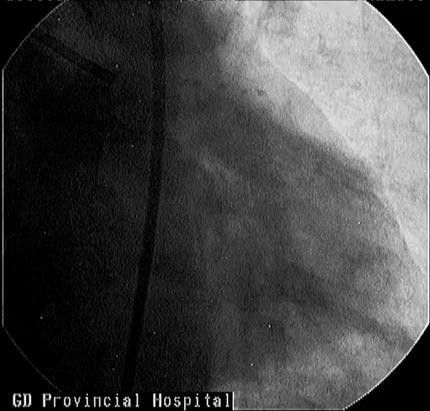

腹主动脉造影

腹主动脉造影发现,腹主动脉中段见一瘤样扩张约50-70mm*30-40mm,右肾动脉近段狭窄60-70%。最终诊断:腹主动脉瘤合并冠状动脉左主干+三支血管病变明确。